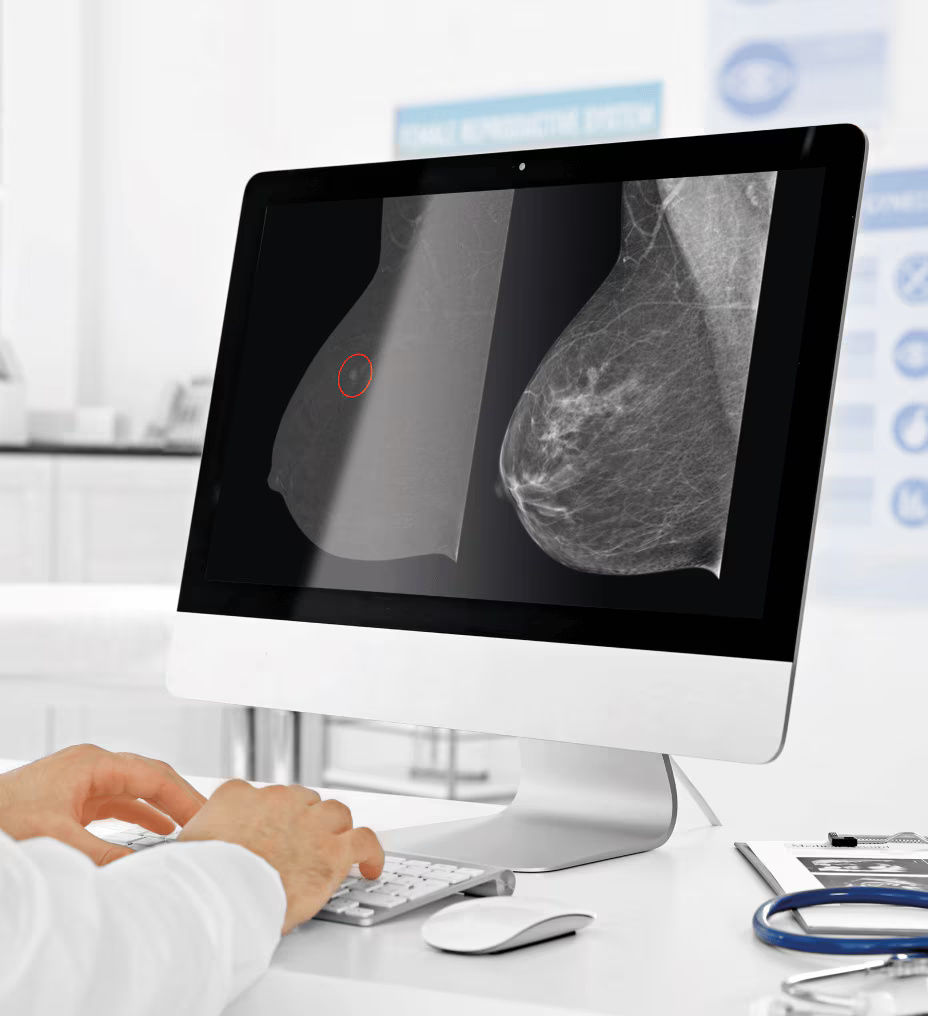

See differently, see clearly, see in contrast

Provide answers to your patients right away and help them avoid the agonizing wait that comes with an inconclusive exam. Don’t seek, see. Accelerate your ability to make a confident diagnosis.